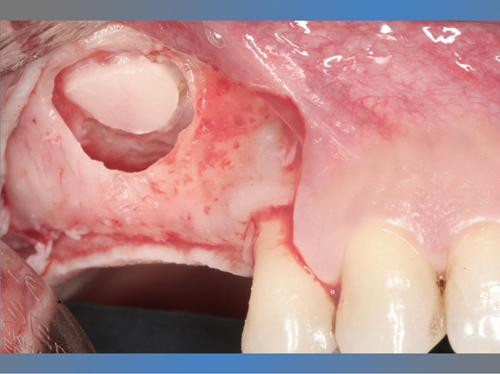

En el maxilar superior tenía poco hueso debido a la presencia del seno maxilar, por lo que se le trato con la técnica de injerto óseo conocida como elevación de seno directa para poder colocarle implantes.